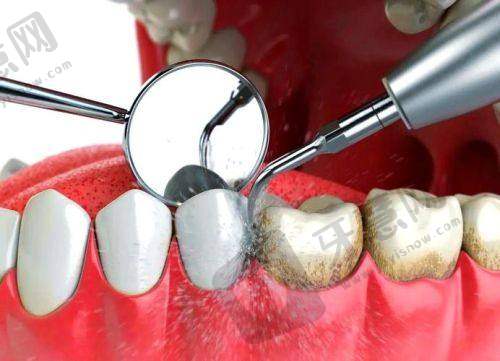

郭佳星医生专精能力突出,他擅长美学修复、牙体牙髓的诊断治疗及口内缺失牙齿种植治疗等,同时也擅长治疗牙周病、牙体牙髓病等疾病。在诊疗过程中,他始终以患者为中 心,注重个性化诊疗方案的制定。有家长带孩子找他补牙,评价其技术好,对待小朋友有耐心,补牙又快又好。还有患者带孩子做反颌矫正,经工作人员推荐找到郭主事(推测为郭佳星),体验良好。总体而言,郭佳星医生凭借专精技术和良好态度,深受患者认可。